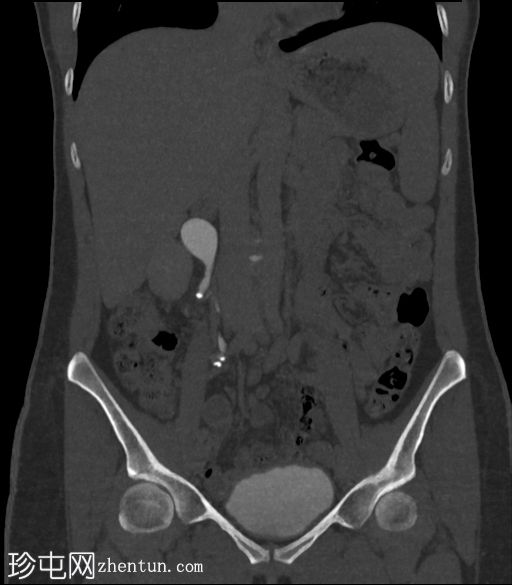

冠状位

平扫

右侧输尿管上段可见一小块高密度结石(约1500 HU)

近端输尿管及右侧肾盂肾盏系统中度扩张

右髂窝内可见多个小钙化结节,符合钙化淋巴结的特征